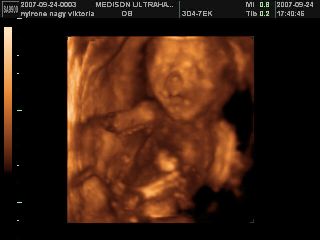

Na megjöttünk az uh-ról, 17 órára volt időpontunk, de majd fél órát csúszott a dolog, mert a doki később tudott bejönni! Minden rendben van, mindene magvan, annyi, amennyinek lennie kell, normál a szíve, a vesék rendben, gyomortelítődés van, méhlepény a fundusban, köldökzsinór 3 erű, viszont nem igen látszott, hogy milyen nemű! A doki szerint inkább lány, mint fiú, de egyáltalán nem mondta egyértelműre, és nem is látszott, összeszorította a lábacskáit a kis szégyenlős! :lol: De a lényeg az, hogy egészséges, és végre láttam az arcát is! :D